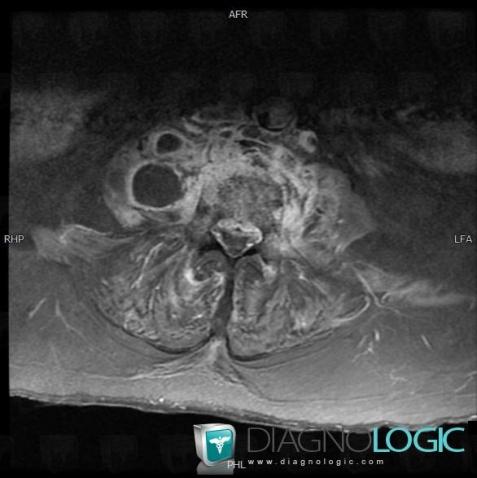

Abscess, Retroperitoneum, MRI

Here is the specific information in the key image above:

- Diagnosis Abscess, Location(s) Retroperitoneum, with gamuts Lesion in the psoas space